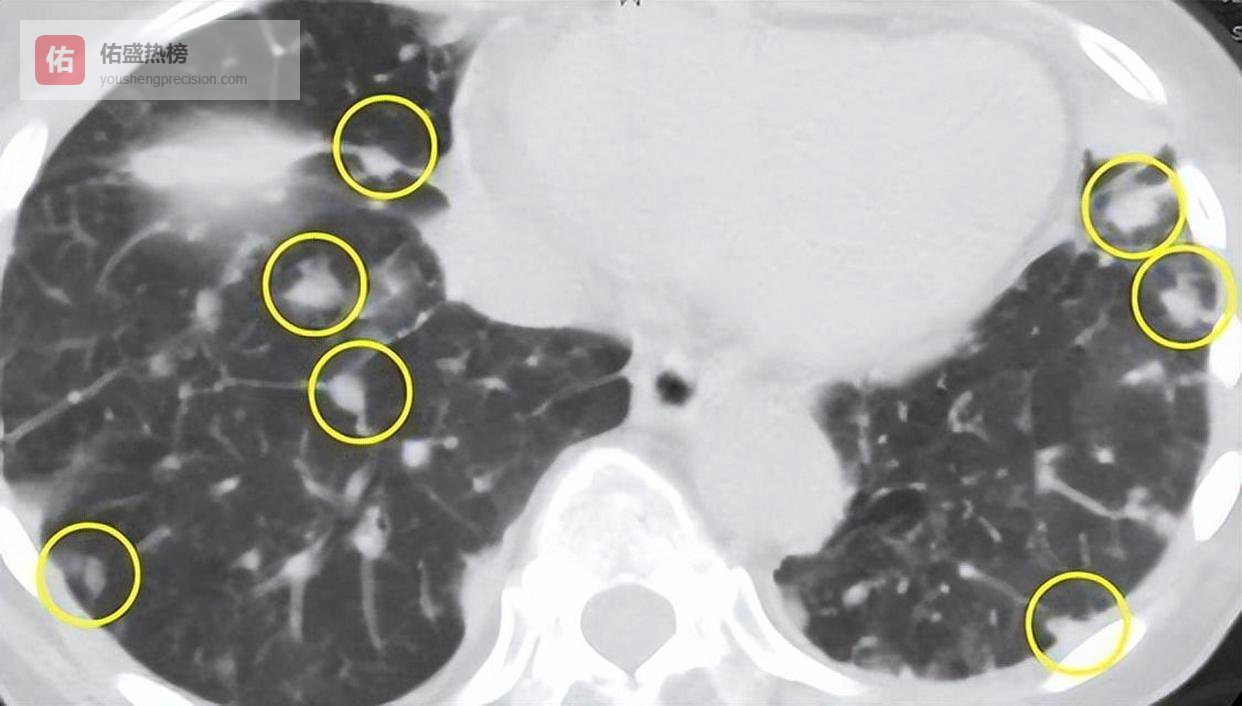

有人此时会问:“那喉咙不舒服总是大毛病吗?”当然不是。但关键在于“反复”和“迁延”。正常咽炎一般7~10天可愈,若你咽部不适超过3周,尤其合并干咳、气短、背痛、声音改变这些症状时,一定不能掉以轻心,要进行肺部影像学检查了。

很多城市每年都做健康体检,可多数人只求血脂、血糖、心电图,而忽略了像“胸部低剂量螺旋CT”这样关乎肺健康的关键筛查。

某项中国肺癌早筛研究发现,这种无创、几分钟就能完成的检查,使得肺癌早诊率提升超过30%。对于年过五十、有吸烟家族史或职业粉尘接触背景者来说,这几分钟,换得的可能是一生清白安宁。